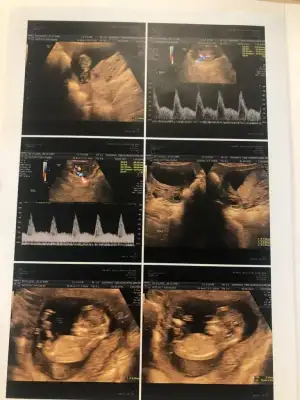

dün 2 li tarama testine girdim bebeğim uyuyordu doktor cinsiyet tahmini yapmadı renkli ultrasonografi görüntülerim var, bu resimlere göre cinsiyet tahmini yapabilirmsiiniz , bu ikinci gebeliğim 8,5 yaşında bir kızım var

mesajım görünmüyor mu acaba cevap alamadım, 12+5 de 2 li tarama yaptırdım, cinsiyet tahmini yapmadılar, bu görüntüler üzerinden tahmin yapabilirmisiniz

tebrik ederim doktor dahil kimsenin göremediğini siz görmüşsünüz 4. aydan sonra anladılar bebeğin erkek olduğunu

Yaaa çok teşekkür ederim 💙😍 sağlıkla gelsin oğlusun 🥰 anketim oylarsaniz sevinirim 🥰